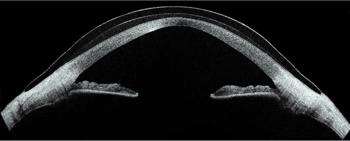

Advancements in lathing techniques and high oxygen-permeable materials have enabled the manufacture of complex, customisable lenses without compromising corneal health (Fig1). Furthermore, developments in ophthalmic instrumentation have simplified the scleral lens fitting procedure for practitioners and enhanced the precision of fit. Accurate estimates of scleral curvature and sagittal depth of the landing zone have led to an increase in successfully fitting the first lens. Increased accessibility to technology, such as anterior OCT, has facilitated non-invasive in-vivo examination of scleral lens fit on the conjunctiva and cornea, improving fit precision and troubleshooting capabilities.

Fig.1: Scleral contact lens